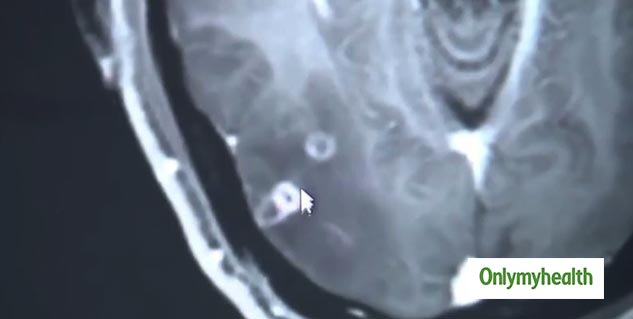

अस्पताल के संक्रमण विभाग के डॉ. वांग जियान-रोंग ने जब झु की चिकित्सा जांच की तो उन्होंने झु में टीनियता (taeniasis) रोग पाया। उन्होंने झु के पूरे शरूर में 700 से ज्यादा टेपवॉर्म पाए।

टेपवॉर्म हमारे शरीर में आमतौर पर संक्रमित पोर्क ( जिसे सही तरीके से नहीं पकाया गया हो) में मौजूद टेपवॉर्म के अंडे खाने से आते हैं। डॉ. वांग का कहना है कि मरीज के मस्तिष्क में बहुत सी जगह में इन टेपवॉर्म के होने की बात सामने आई है।

उन्होंने कहा, ''मरीज के फेफड़ों और मांसपेशियों में भी टेपवॉर्म भरे हुए थे, जिसके कारण सीने में जकड़न की शिकायत थी।'' उन्होंने कहा कि वॉर्म पहले ही मरीज के अंगों को काफी नुकसान पहुंचा चुके हैं।